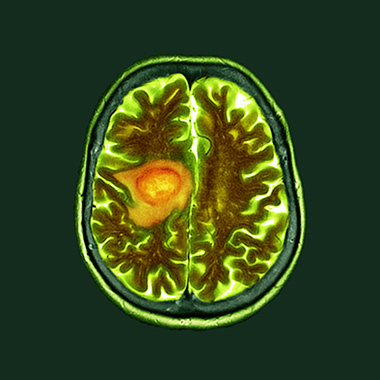

Pyrimidine synthesis is a liability in IDH-mutant gliomas

Therapies in tumors with mutations in isocitrate dehydrogenase-1 and -2 (mtIDH1/2) have so far focused on inhibiting the neomorphic activity of the mutant enzyme, but mtIDH1/2 also imposes other metabolic liabilities. Using a screen of metabolic inhibitors, Samuel McBrayer, Ph.D., and colleagues identified the pyrimidine synthesis pathway as a targetable vulnerability in this subset of gliomas. They report that a brain-penetrant pyrimidine synthesis inhibitor reduces tumor growth in novel mouse models of mtIDH1/2-driven glioma. The work has stimulated efforts to target this pathway in clinical trials.